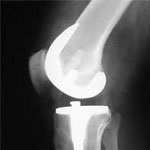

8) Mostafa Shahrezaee, Mahmoud Jabalameli, Abolfazl Noori, Seyed Reza Sharifzadeh, Mehran Setareh,Tahmineh Mokhtari and Fatemeh Jafari. Accuracy of Lower Limb Alignment in Patients with Total Knee Arthroplasty in Fajr Hospital, Tehran, 2008-2013. BIOSCIENCES BIOTECHNOLOGY RESEARCH ASIA. 2014; 11(2), 807-813

14) محمد تقی طهماسبی، آرش متقی، مصطفی شاهرضایی. تعویض مفصل زانو در بیماران مبتلا به آرتروز زانو: نتایج 34 مورد. مجله دانشکده پزشکی، دانشگاه علوم پزشکی تهران، دوره 67، شماره 2، اردیبهشت 1388، صفحات 146-150